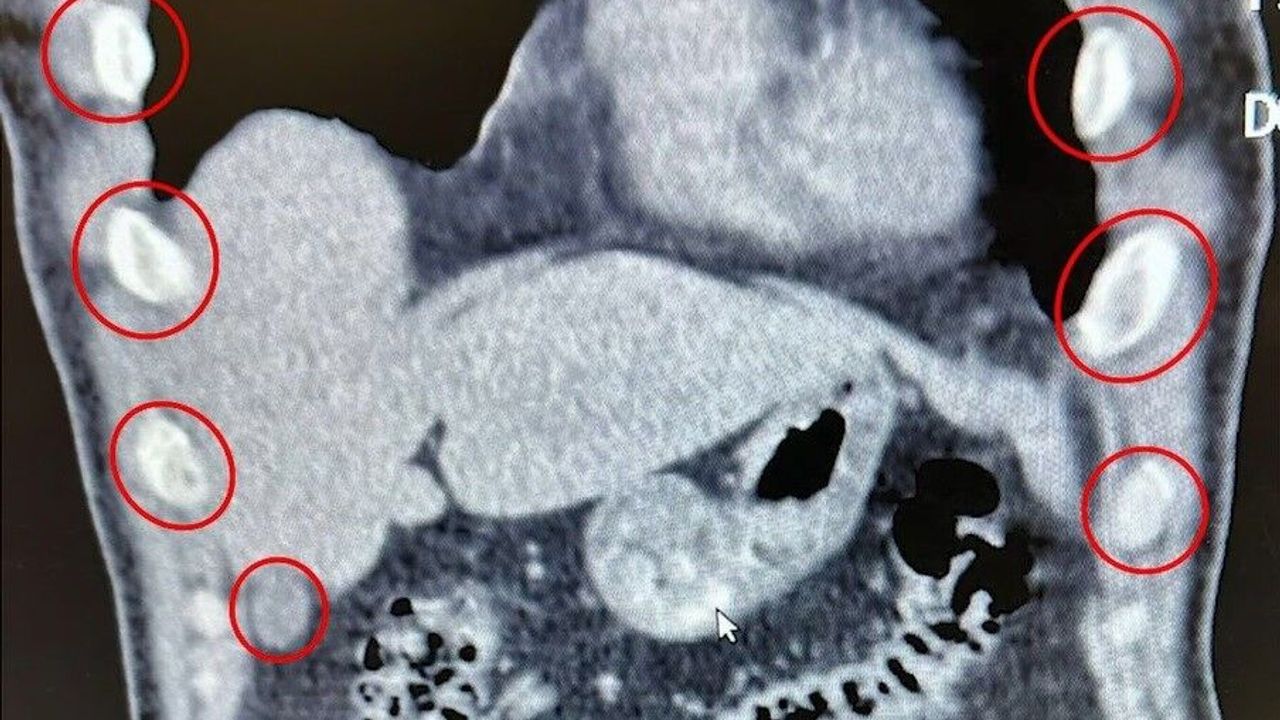

Bitlis İl Emniyet Müdürlüğü Narkotik Suçlarla Mücadele Şube Müdürlüğü ekipleri, uyuşturucu ile mücadele kapsamında önemli bir operasyona imza attı. Tatvan ilçesinde durdurulan bir otobüste yolcu olarak seyahat eden yabancı uyruklu 2 kişi gözaltına alındı. Şahısların yapılan tıbbi müdahalesinde, yuttukları 136 kapsül halinde toplam 1 kilo 48 gram metamfetamin ele geçirildi.